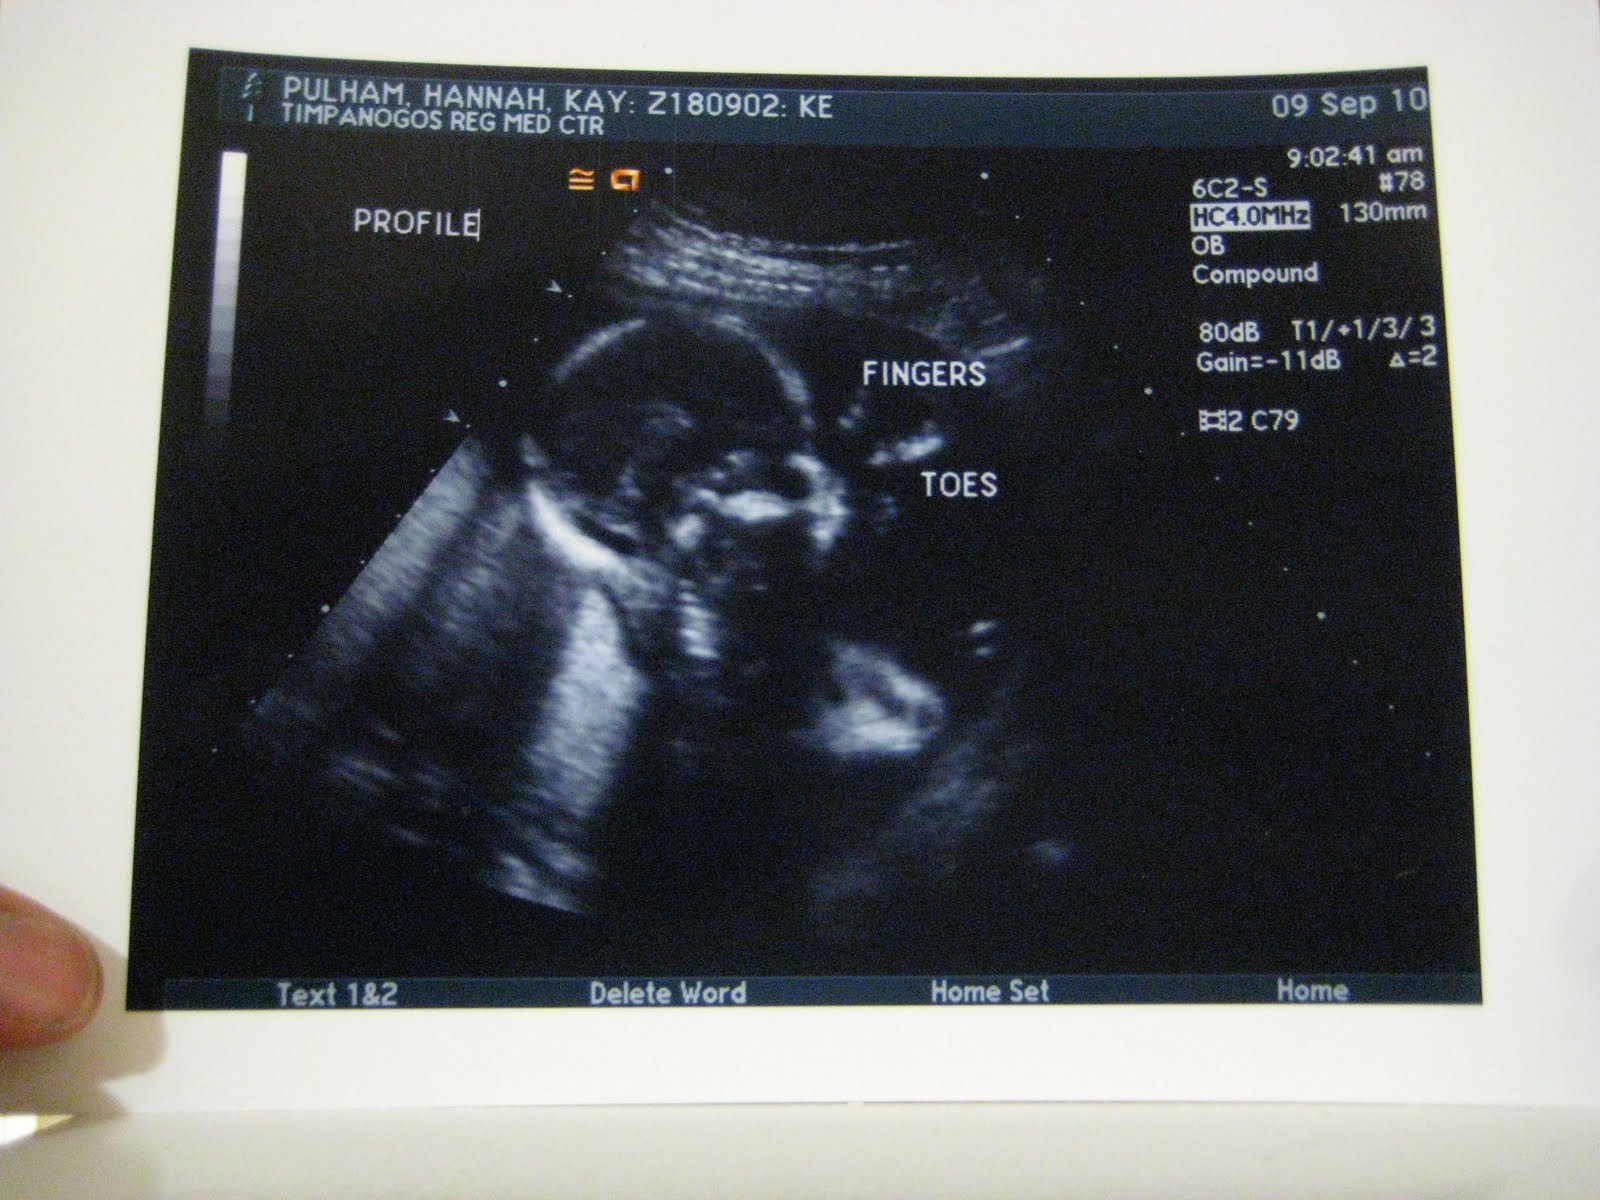

Our little mister at 33 weeks!

Side Profile